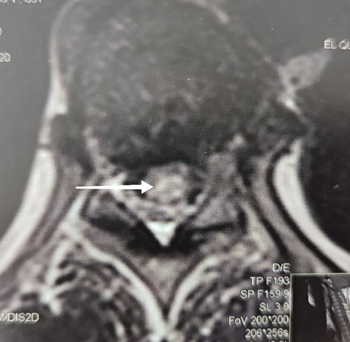

A whole spine MRI (Magnetic Resonance Imaging) revealed an intramedullary hyperintense signal on T2-weighted images extending longitudinally from D6 to D12 and transversally in axial planes. These findings indicated longitudinally extensive transverse myelitis (Figure 1 & 2). T1-weighted images following Gadolinium injection showed mild enhancement.

Figure 2 Axial T2 weighted image (D11 level) showing intramedullary hyperintensity with transverse extension.